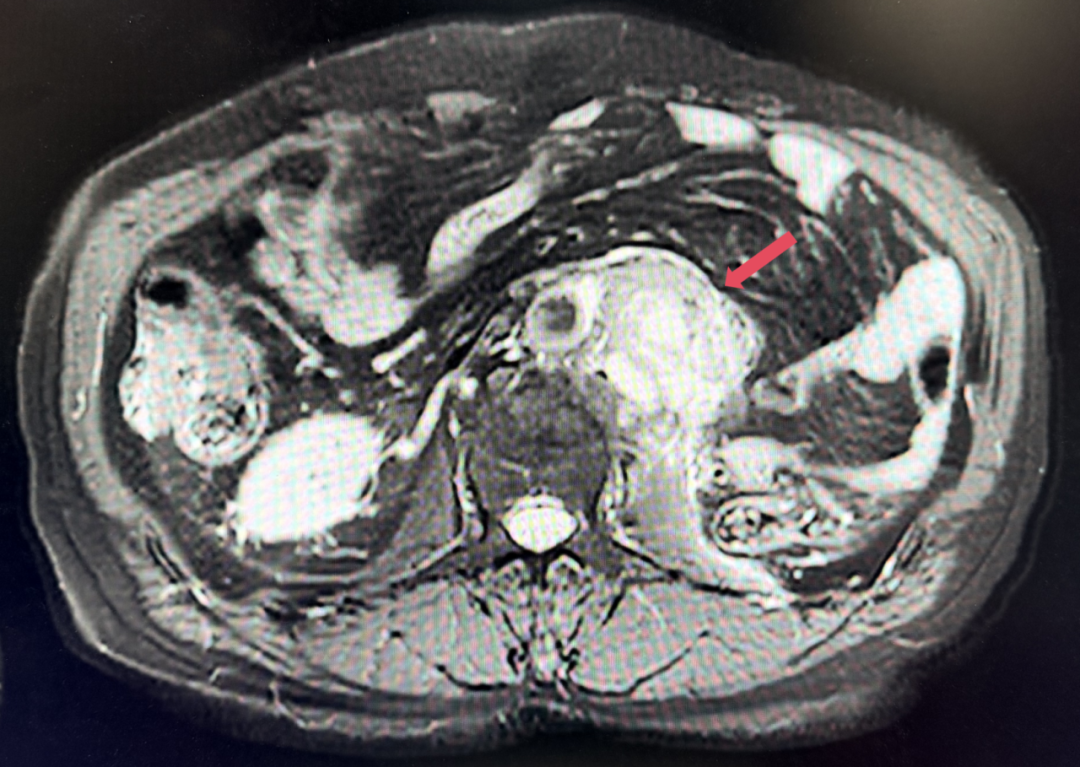

2025年1月:序贯为呋喹替尼单药(5mg,po,qd,D1-14,q3w)治疗。

2026年4月:持续维持PR,PFS超过37个月。

患者初诊时68岁,2020年9月因“体检发现左肾占位2年”行腹腔镜下左肾根治性切除术,术后病理提示为肾透明细胞癌,pT3aN0M0,未行术后辅助治疗、未规律复查。2022年3月胸腹盆CT示腹膜后转移,IMDC评分0分,低危组。随后予一线培唑帕尼治疗,最佳疗效SD,2022年11月PD。于2023年1月经筛选进入Ⅲ期FRUSICA-2临床研究,开始接受呋喹替尼联合信迪利单抗二线治疗,用药6周(C2)后首次肿评即实现疗效PR(缩瘤率40.2%),用药10个月时缩瘤率近七成(68%),并维持上述水平至今,PFS已经超过37个月,在二线治疗中实现了长期无进展生存。同时,患者对呋喹替尼联合信迪利单抗方案耐受性良好,仅见轻微蛋白尿和偶然腹泻,未见其他不良反应,也未见免疫治疗相关不良反应。该方案有望为TKI经治的晚期肾癌患者带来新的选择,为实现长期生存提供可能性。